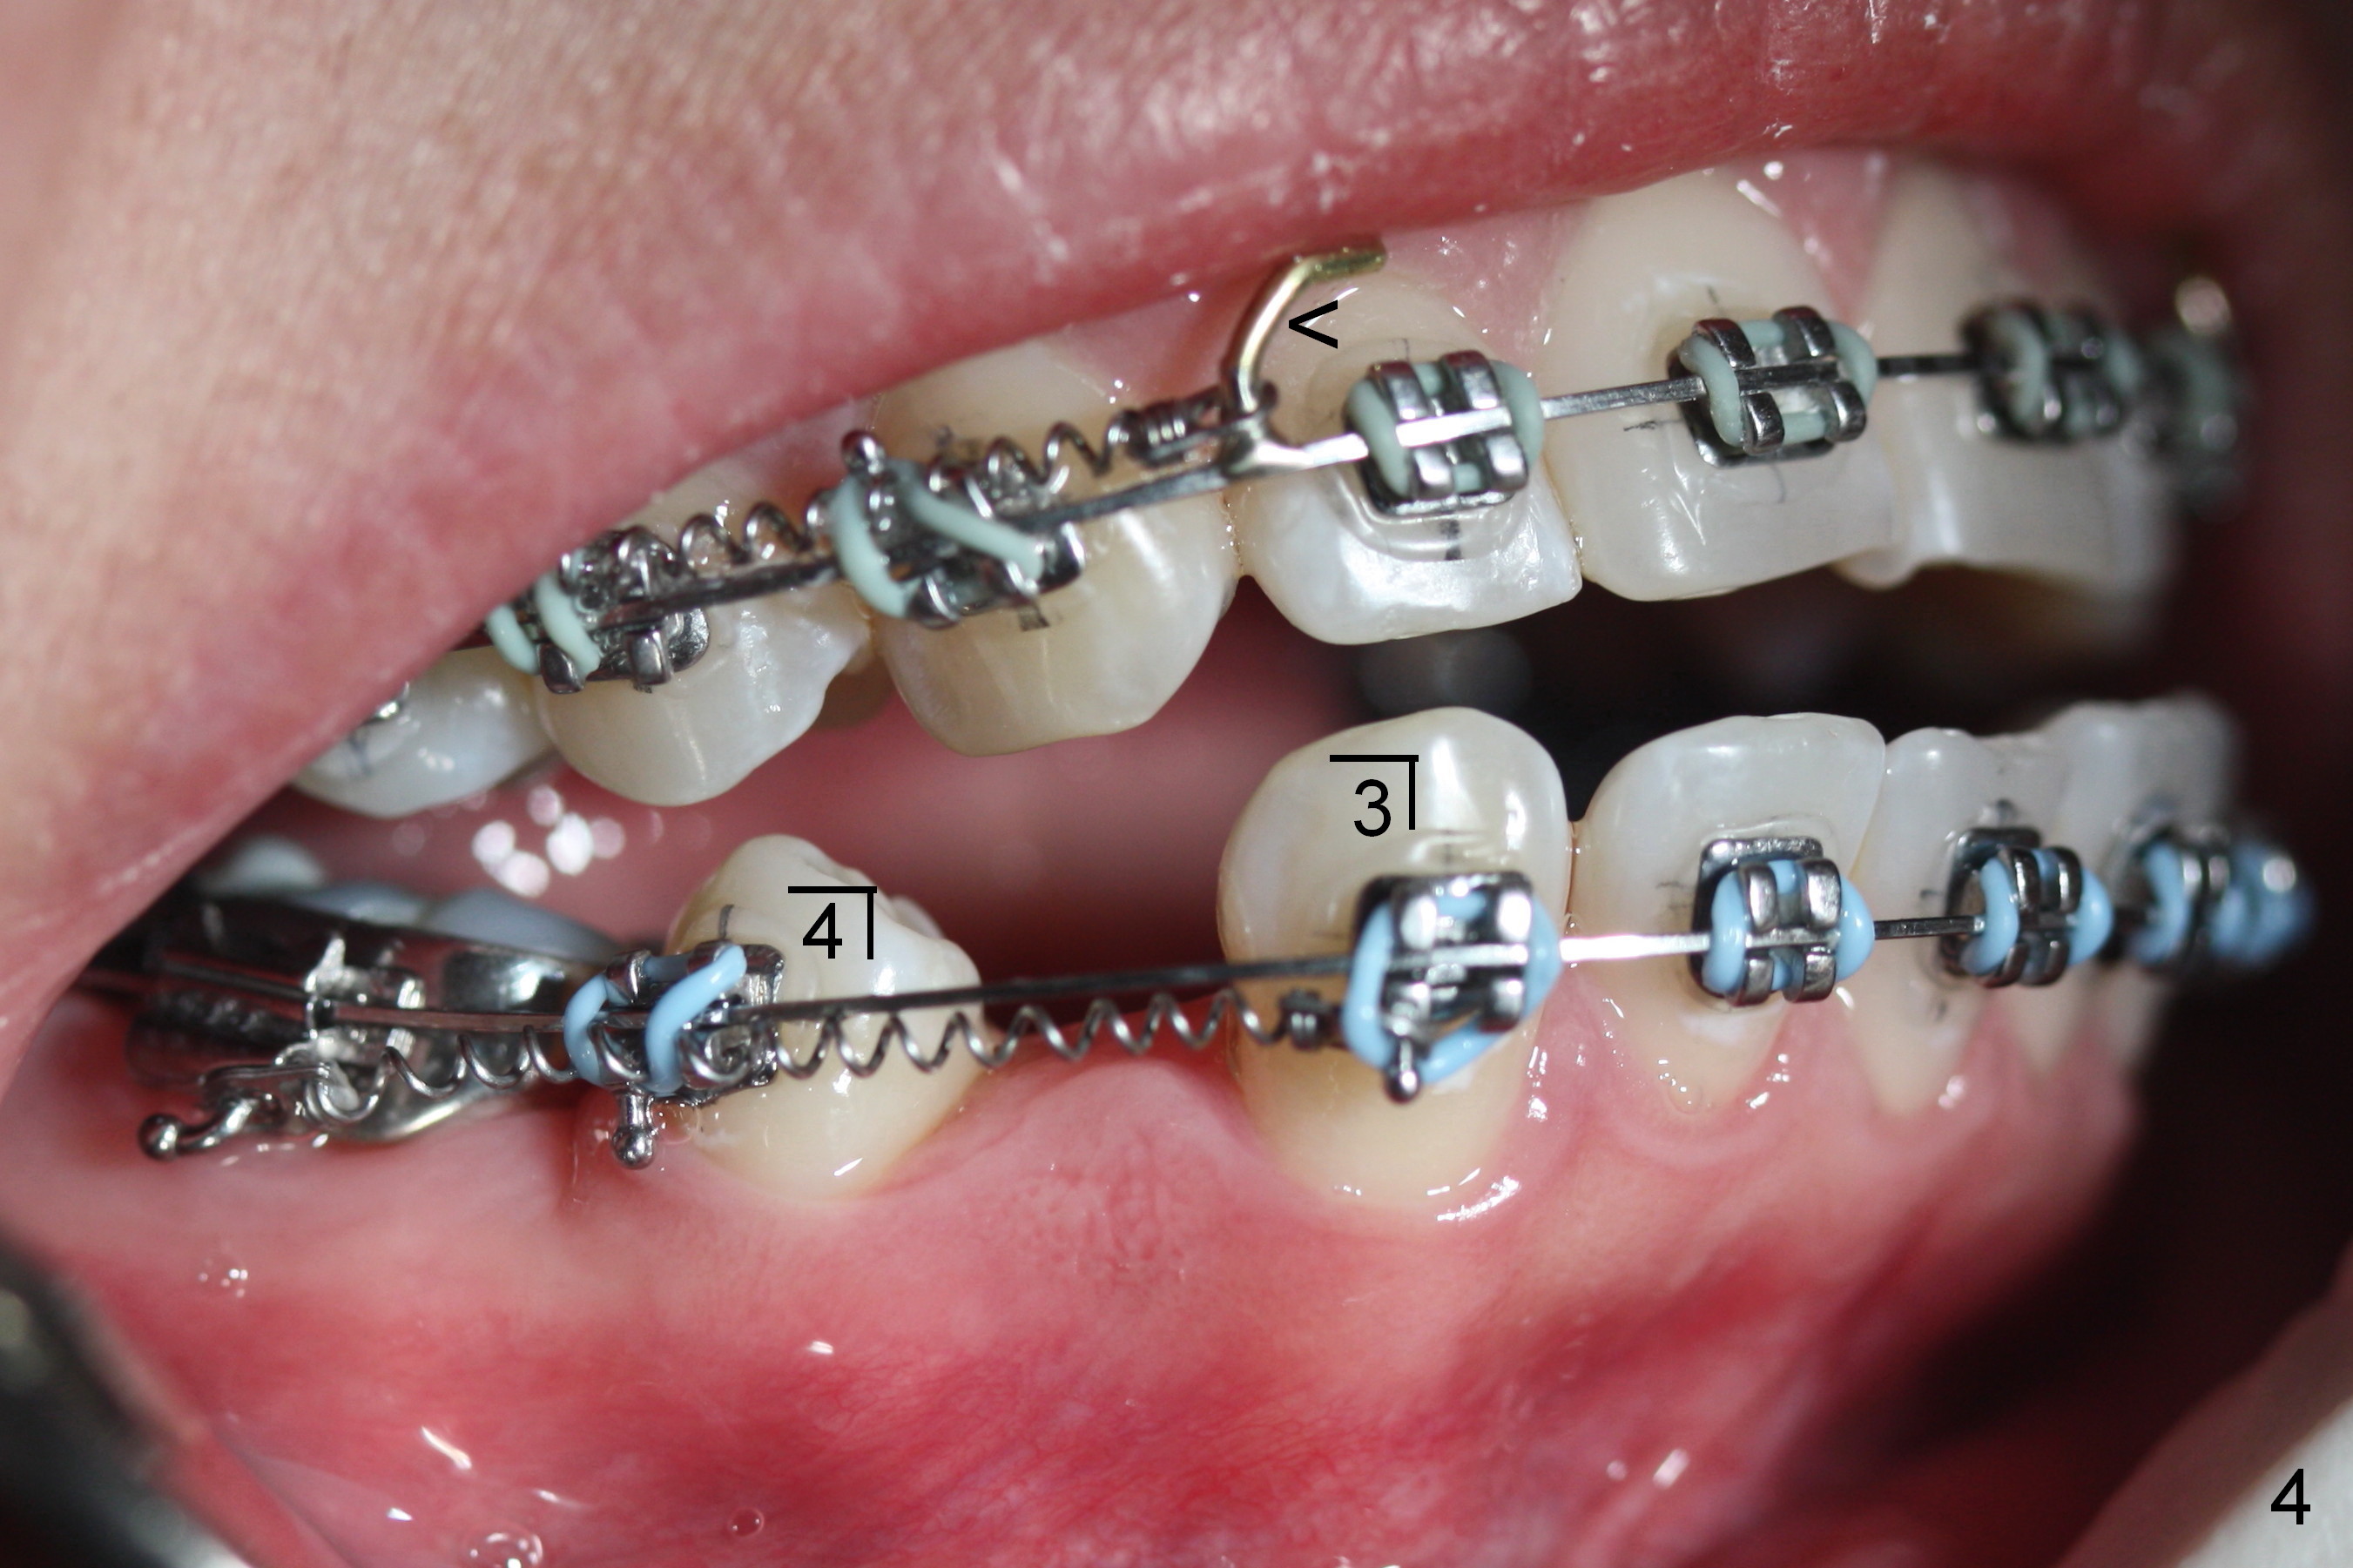

LR4 (Fig.1) and LL3 (Fig.2,3) are distalized 7.5 months of ortho treatment (1,2). Next step is to retract LR3 with closed coil spring (Fig.4) and de-rotate LL3 with a rotation wedge (Fig.5 *). The upper arch appears to be slightly in cross bite (Fig.4) 2 months after closed coil springs placed between the upper posted wire (<) and mini-implants (placed in the buccal tuberosity). Profile needs to be improved (Fig.6,7).

On March 9, 2016 (11.5 months of treatment), periodontal abscess develops around UR6 (Fig.11 (palatal view) *). It appears that the molar band as well as the buccal tube (Fig.12 *) is embedded into the gingiva. One week after band removal (as well as posted wire and closed coil springs), the infection resolves (Fig.14). As compared to preop Panoramus (Fig.13), the upper arch distalization is mainly at the crown level (Fig.4 arrows). The miniimplants should be placed higher (at the zygomatic arch); the post should be taller. Therefore the roots can be distalized as well (click the link below).